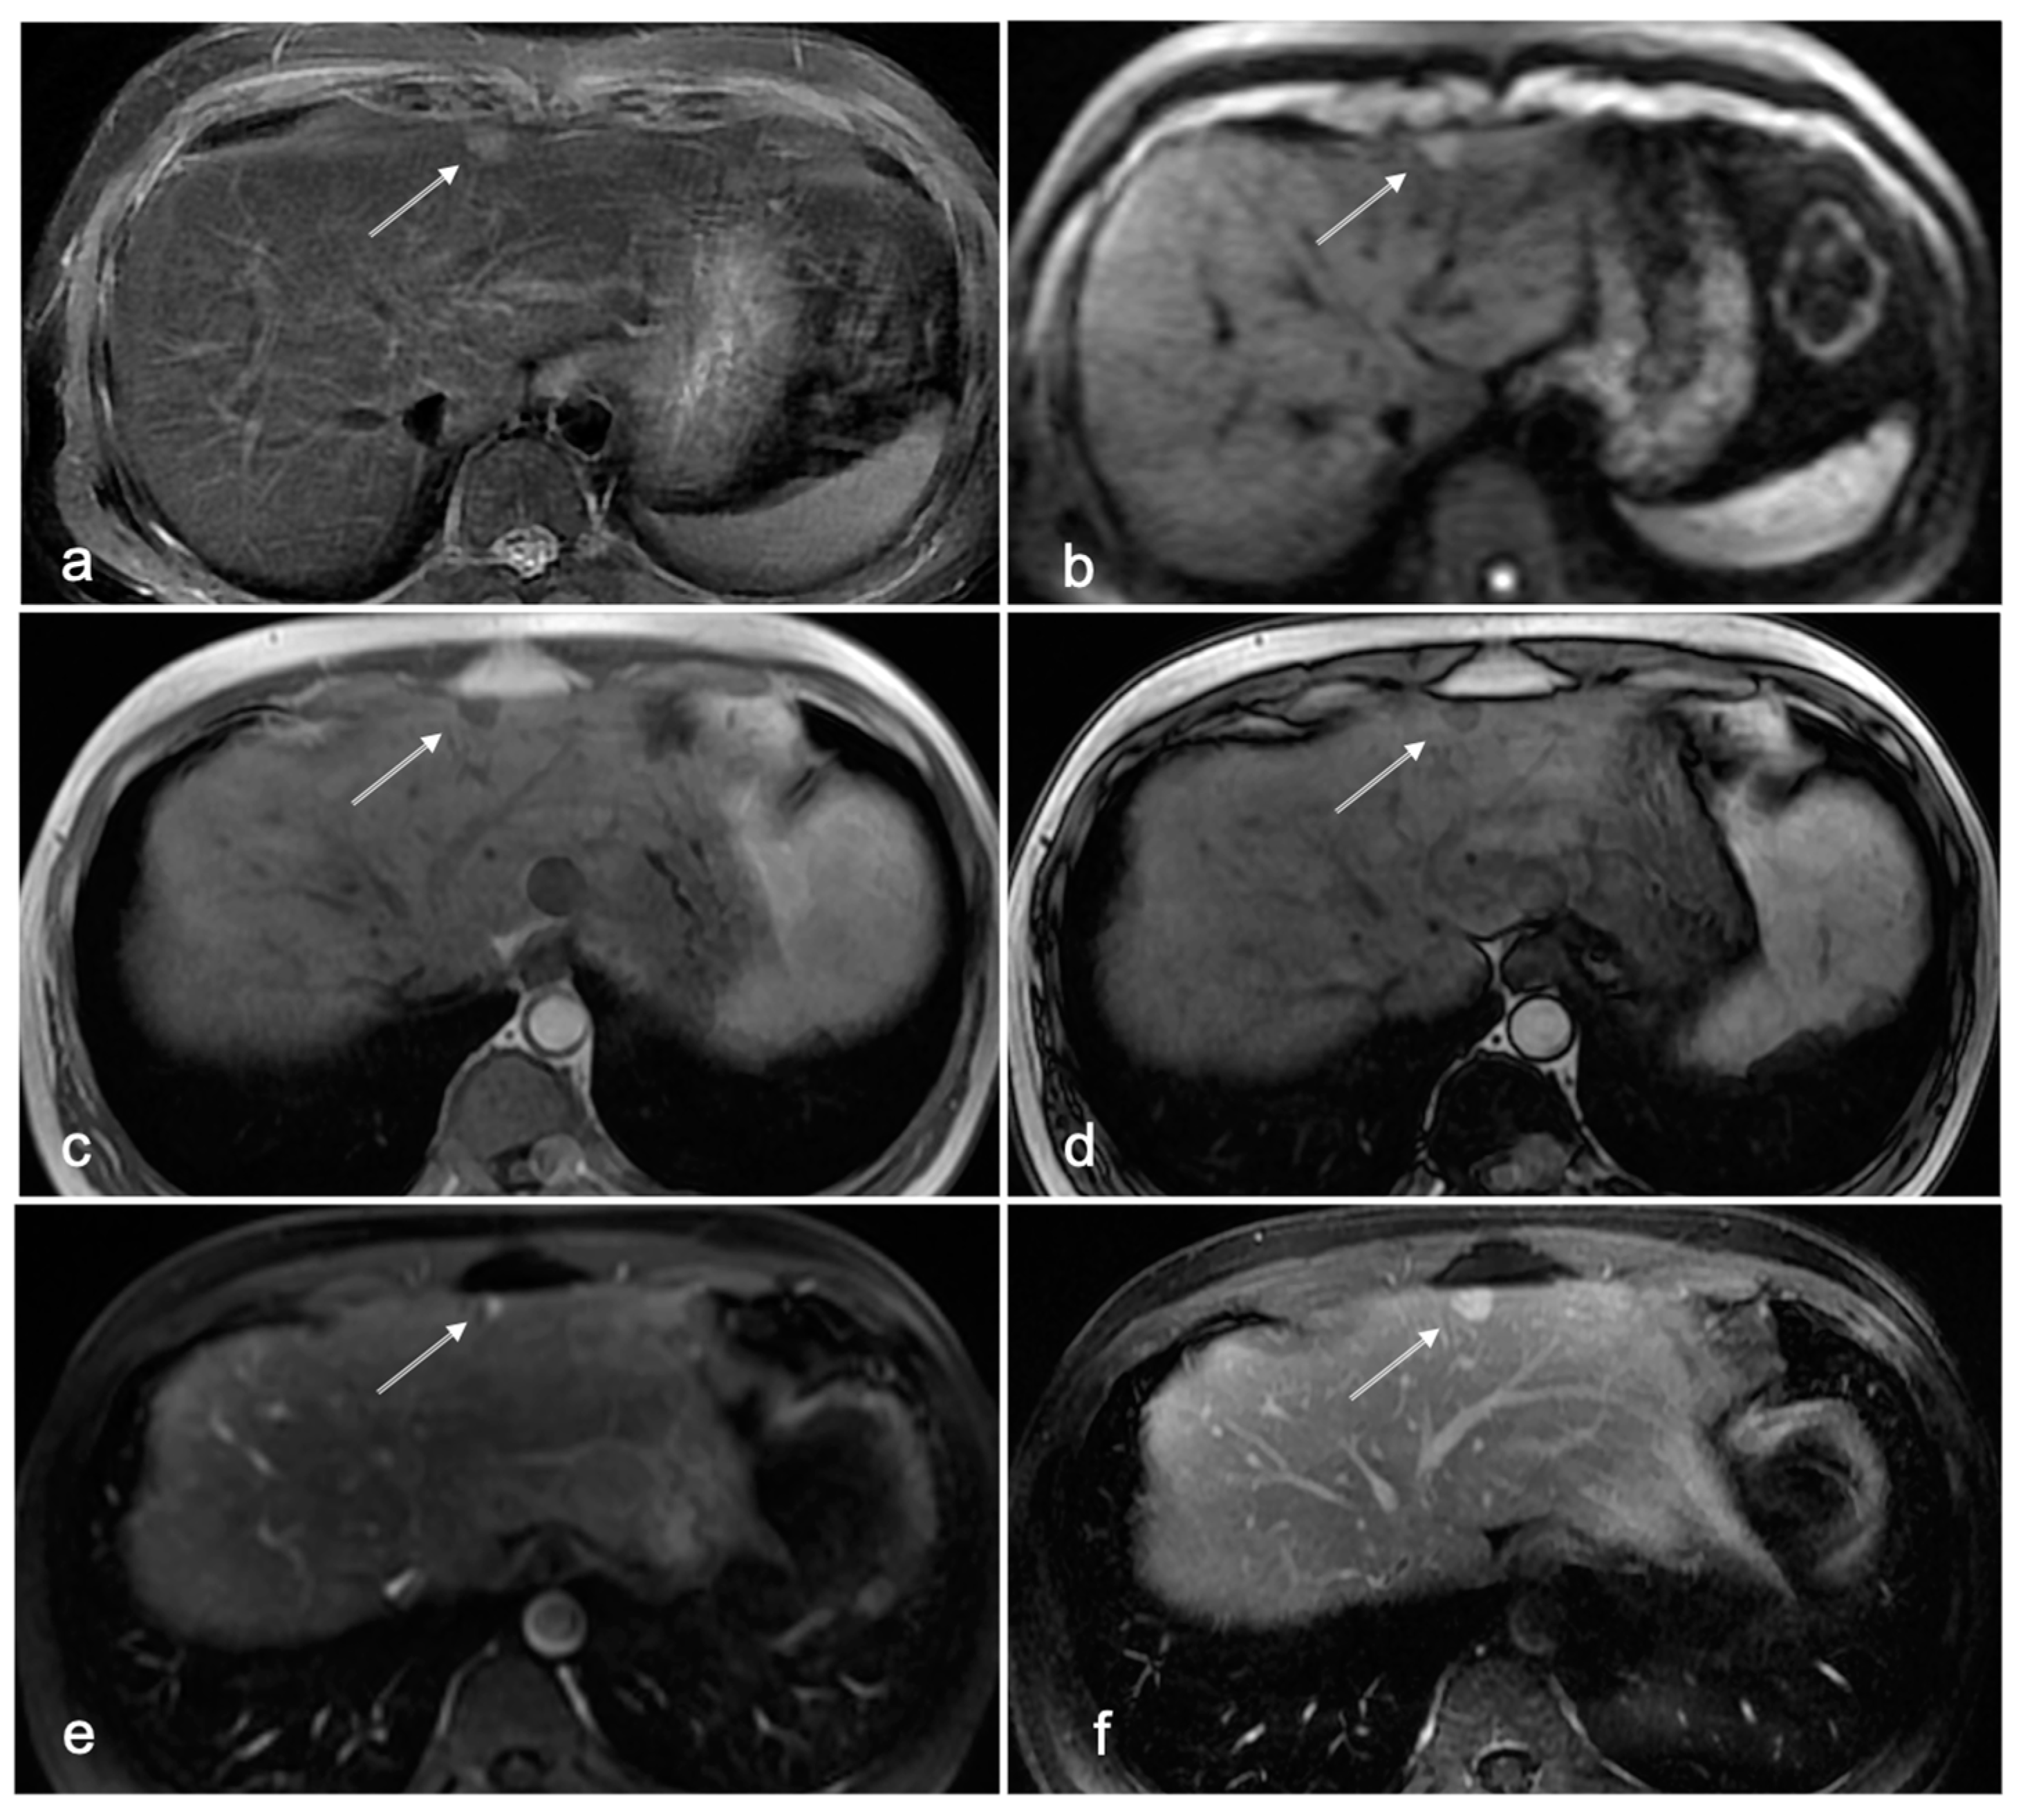

Figure 4.

Forty-one-year-old male patient with chronic HBV infection, without clear signs of cirrhosis. On NC-AMRI axial T2W, FS images (a) and DWI (b) show a mildly hyperintense lesion subcapsular in segment 4 (arrow). The lesion is hypointense on T1W in-phase (c) and opposed-phase (d) images. This lesion was interpreted as suspect for HCC by all readers. On CE-MRI, however, dynamic contrast-enhanced sequences showed characteristic peripheral nodular enhancement in the arterial phase (e) with persistent enhancement in the delayed phase (f) compatible with a benign lesion: hemangioma.

In our study, the readers had no access to prior examinations, which would reflect a (most pessimistic) screening situation in which all patients are considered newly enrolled. For this reason, it is expected that the relatively high false-positive detection rate of 13% will likewise be lower in daily practice when the readers have access to prior studies for a fair comparison. Previously established benign lesions such as (atypical) hemangiomas as illustrated in Figure 4 can then be verified as such. Nonetheless, we wish to emphasize that, with screening for HCC, all doubtful lesions would qualify for confirmative diagnosis with full MRI liver protocol. After confirmation of the benign nature (Li-RADS 1 and 2) of the lesions, the patient may proceed with the regular surveillance schedule using NC-AMRI.